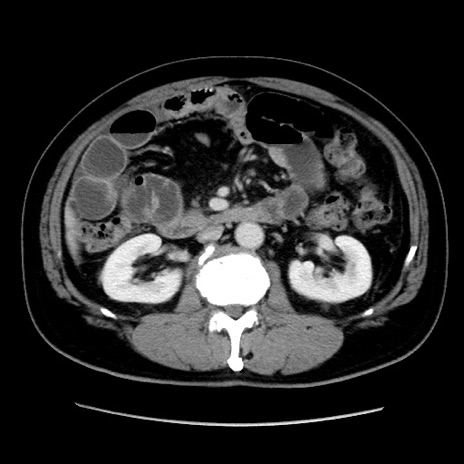

冠状断像

症例16(横断像)

【症例】 70歳代男性

【主訴】 腹痛、嘔吐

【現病歴】 約1ヶ月前より間欠的に腹痛と嘔吐あり、当院消化器内科を受診したところCTで多発する肝臓のLDAを指摘され、精査中であった。以降は消化器症状は安定していたが、2日前より嘔気と腹痛があり、同日より排便・排ガスが消失した。改善認めず、 本日、救急外来を受診した。

【既往歴】 大腸ポリープ切除後。

【身体所見】意識清明・会話良好、BT 36.3℃、BP 127/80mmHg、 P 80bpm、腹部:膨満あり、平坦・軟、上腹部正中および下腹部正中に圧痛あり、反跳痛なし、筋性防御なし。

【データ】WBC 7200、CRP 0.77